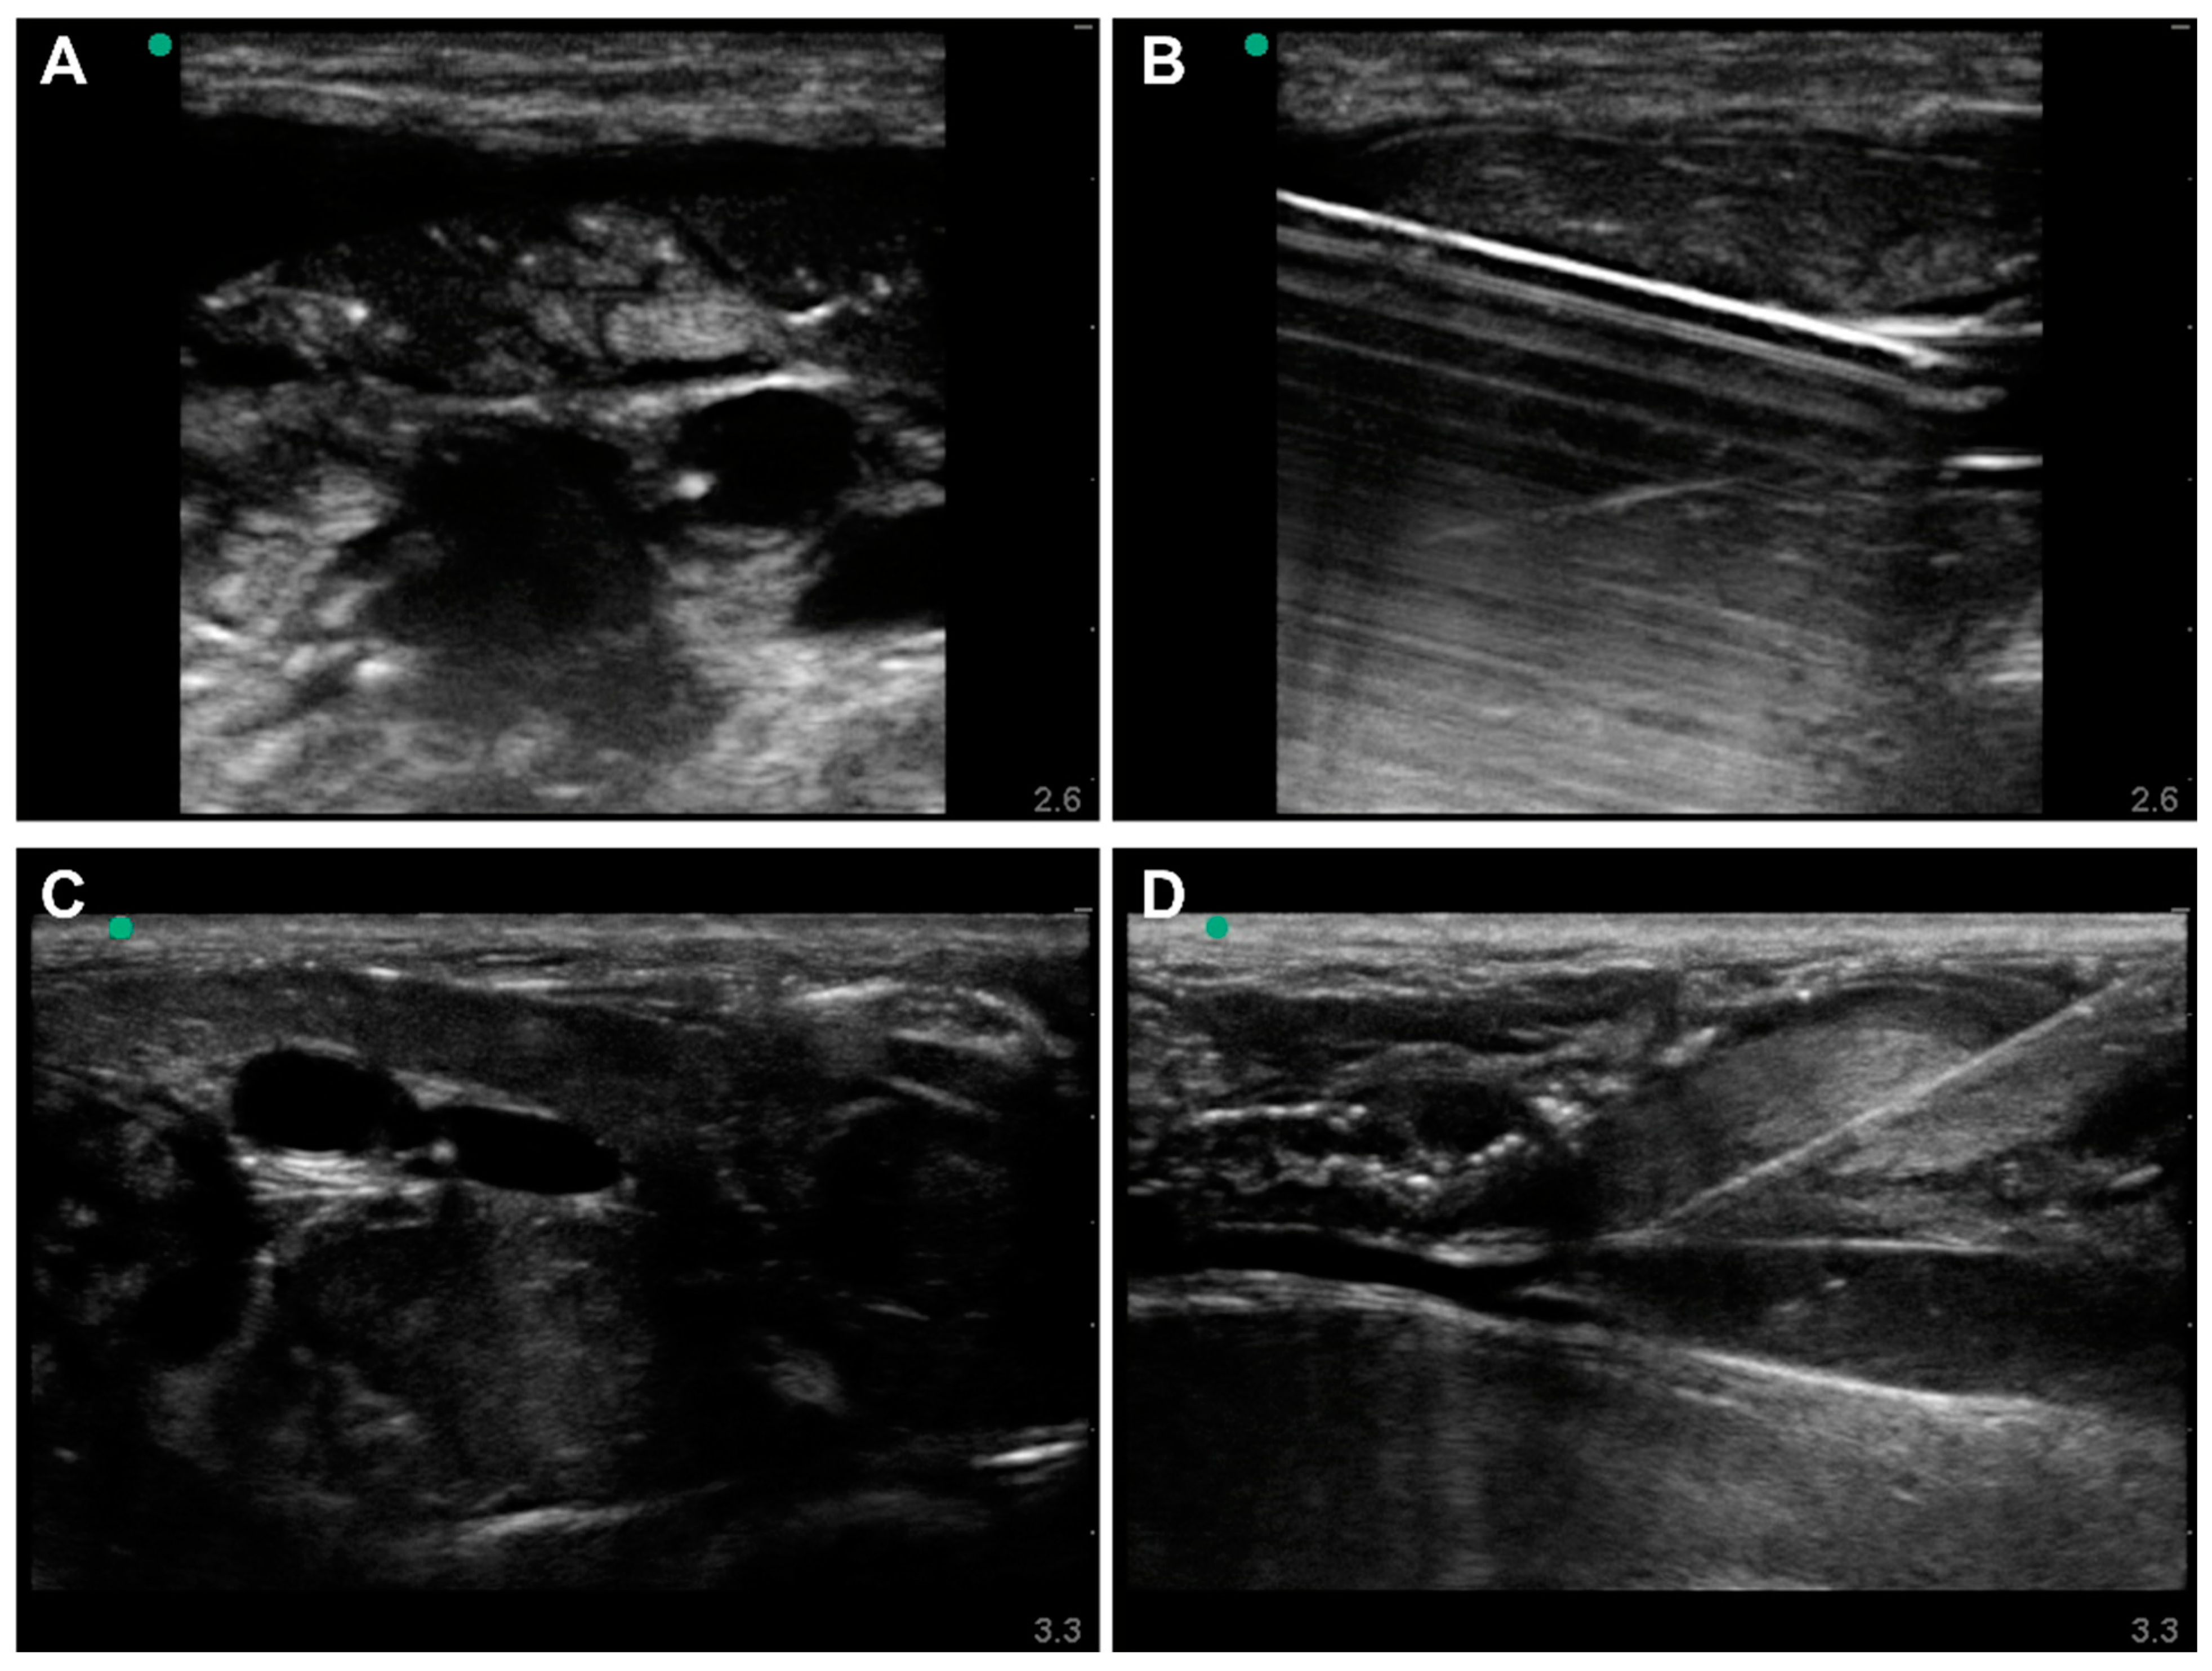

2.3. Lower-Body Ex Vivo Porcine Model

2.4. Ultrasound Imaging and Vascular Access

3.2. Lower-Body Ex Vivo Porcine Model Results